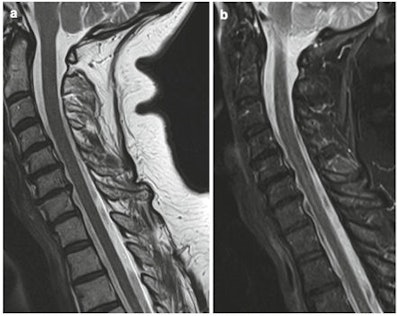

Sagittal T1-weighted (A) and STIR (B) MR images show small disc bulges and disc dehydration at multiple levels in keeping with degenerative change. All images courtesy of Prof. Rajesh Botchu.